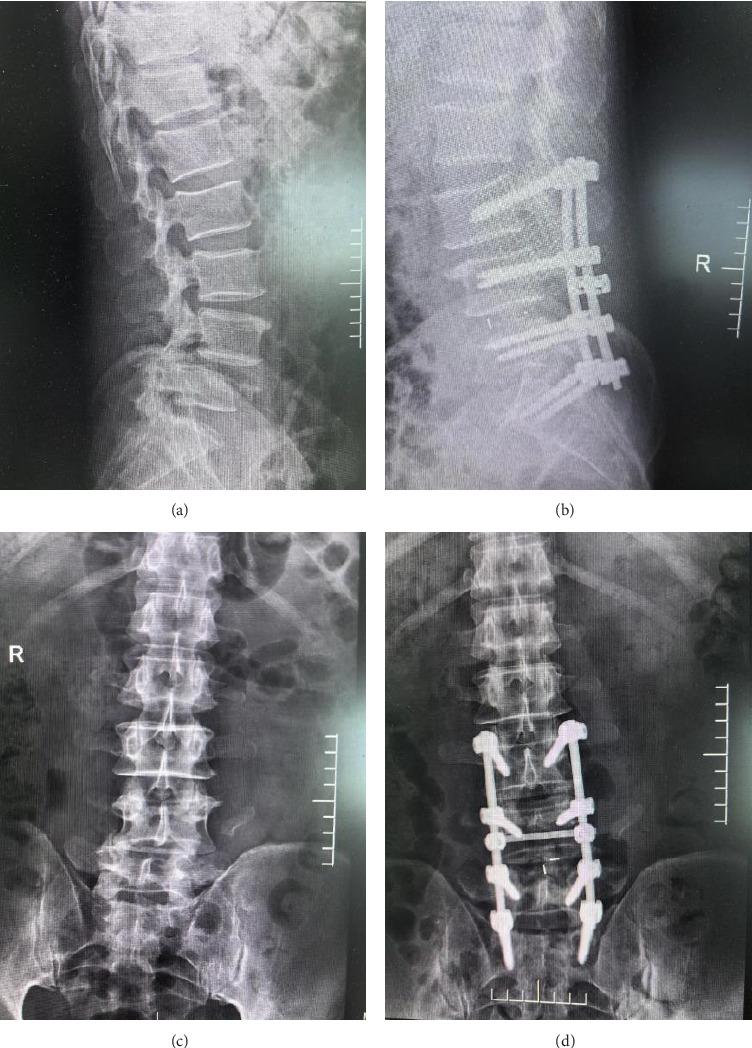

This study evaluates the effectiveness and timeliness of posterior decompression and internal fixation in the emergency management of thoracolumbar fractures complicated by spinal cord injuries. We retrospectively analyzed 40 patients treated at our hospital from January 2019 to February 2022. Each patient underwent posterior decompression and internal fixation, with preoperative and postoperative assessments including vertebral body height, American Spinal Injury Association (ASIA) score, Visual Analog Scale (VAS) score, and urodynamic indices. Postoperative improvements were noted in vertebral body height, with anterior and posterior heights increasing to 12.82 (± 1.23) mm and 3.21 (± 0.64) mm, respectively, and kyphosis angle improving to 14.26 (± 0.32). Significant enhancements were also observed in motor (from 40.78 [± 4.32] to 59.86 [± 1.37]) and sensory (from 45.98 [± 3.20] to 66.92 [± 1.28]) function scores, and a reduction in VAS score from 6.89 (± 0.78) to 1.78 (± 0.32). Urodynamic measurements showed increased maximum urine flow and detrusor pressure postintervention. All surgical wounds healed within two weeks without significant complications. Posterior decompression and internal fixation significantly improve spinal stability, pain, motor, and sensory functions in patients with thoracolumbar fractures and spinal cord injuries, demonstrating its effectiveness and clinical utility.

本研究评估了后路减压内固定术在胸腰椎骨折合并脊髓损伤急诊治疗中的有效性和及时性。我们回顾性分析了2019年1月至2022年2月在我院接受治疗的40例患者。每位患者均接受了后路减压内固定术,术前和术后评估包括椎体高度、美国脊髓损伤协会(ASIA)评分、视觉模拟量表(VAS)评分和尿动力学指标。术后椎体高度有所改善,前、后高度分别增加至12.82(±1.23)mm和3.21(±0.64)mm,后凸角改善至14.26(±0.32)。运动(从40.78[±4.32]提高到59.86[±1.37])和感觉(从45.98[±3.20]提高到66.92[±1.28])功能评分也有显著提高,VAS评分从6.89(±0.78)降低到1.78(±0.32)。尿动力学测量显示干预后最大尿流率和逼尿肌压力增加。所有手术伤口均在两周内愈合,无明显并发症。后路减压内固定术可显著改善胸腰椎骨折合并脊髓损伤患者的脊柱稳定性、疼痛、运动和感觉功能,证明了其有效性和临床实用性。